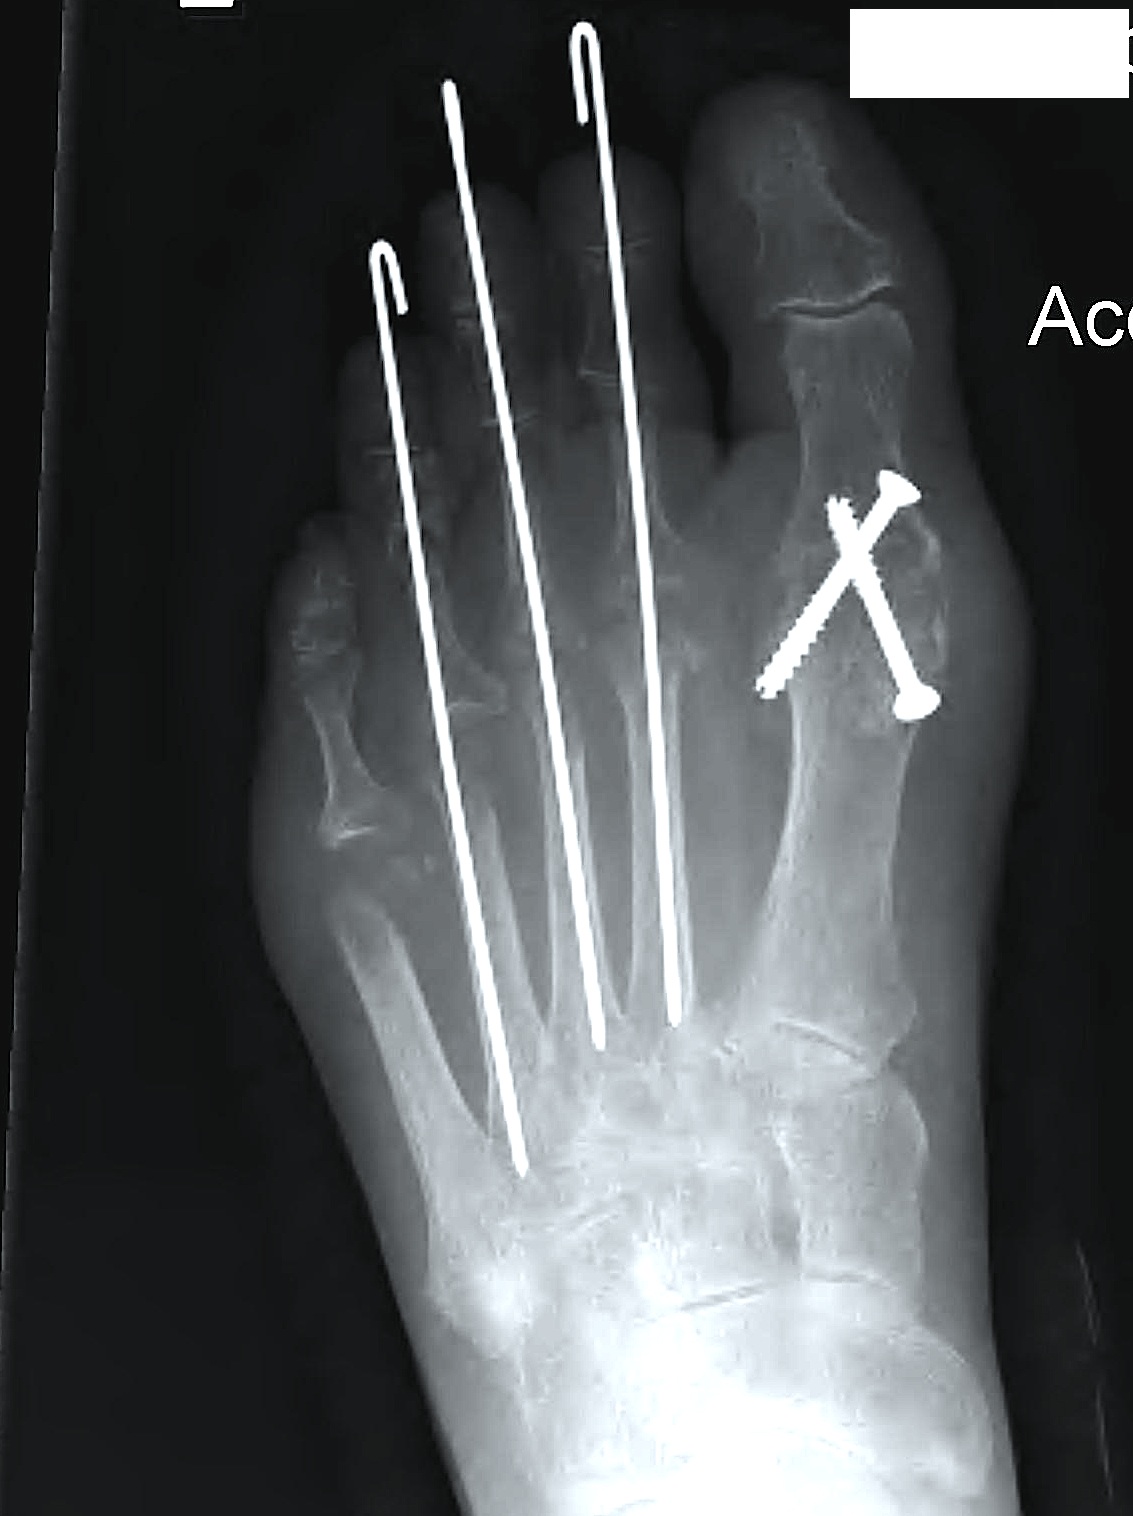

Operative Options

Osteotomy / Arthrodesis / Arthroplasty / Keller's procedure (excision arthroplasty)

Dai et al Zhongguo Gu Shang 2012

- 1st MTPJ fusion in 129 feet with RA

- 3% nonunion

He et al J Foot Ankle Surg 2021

- systematic review of 1st MTPJ arthrodesis v arthroplasty in RA

- no difference in pain score, outcome, or reoperation rates

- complications of Keller procedure

- hallux valgus, cock up, flail toe

- reserve for salvage only